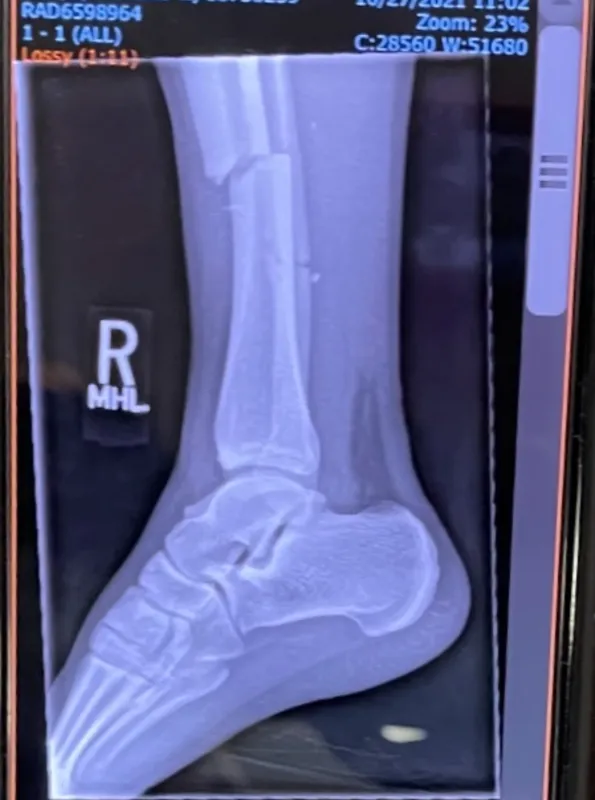

“When I lifted my leg up, I could see bone sticking out, and where my toes were supposed to be, I saw my heel. My leg was in an L shape,” he says. “It was the most pain I’d ever felt. It was like someone took a chainsaw through my leg and then put it in a bonfire. At that point, I passed out.”

Later at University of Iowa Health Care, Phelps remembers talking to Matthew Karam, MD, an orthopedic surgeon who recommended same-day surgery to insert a titanium rod to stabilize the tibia. Both the tibia and the smaller fibula in Phelps’s right leg were broken.

“Dr. Karam told me that due to the possibility of compartment syndrome there was a 10% chance of leg amputation. And that’s when I broke down crying. I called my dad and told him I might never walk again, that this might be it for me,” says Phelps, who is from the western Iowa town of Kingsley. “I never dreamed I’d be able to play football again.”